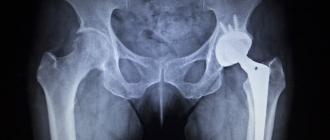

A car accident can create unpredictable injuries in an instant. Recovering from a vehicle crash can be complex and confusing, involving expensive medical bills and time-consuming doctor visits and therapies, all while fighting insurance companies for money you’re owed.